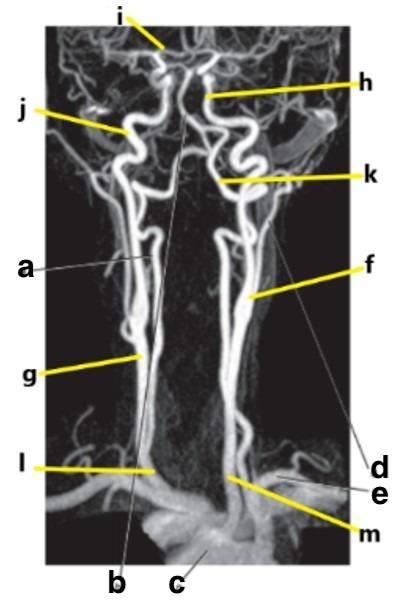

What is letter e?

Subclavian artery

Which letter is the popliteal artery?

A

What is letter f?

Vertebral artery

What is letter a?

What is letter c?

Aortic arch

Which letter is the left common carotid?

Internal carotid artery

What is letter k?

The first vessel to branch off the aortic arch is the:

Brachiocephalic trunk

Which letter is the Right vertebral artery?

f

Ascending aorta

Descending aorta

Carotid bifurcation

What is letter m?

Common carotid artery

External carotid artery

Basilar artery